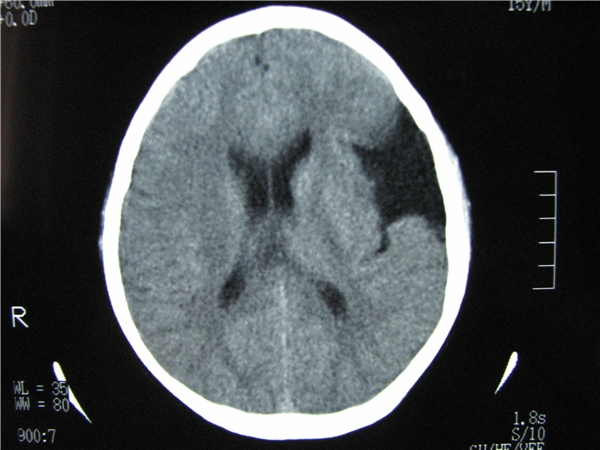

标题: CT20748:M 15Y 头痛,以前有外伤史请老师看看除了囊肿还有别 [打印本页]

标题: CT20748:M 15Y 头痛,以前有外伤史请老师看看除了囊肿还有别

m 15y 头痛,以前有外伤史请老师看看除了囊肿还有别的吗?

双侧侧裂池和纵裂池近前颅窝蛛网膜囊肿。

不能除外脑穿通畸形

无明显占位及负占位效应,考虑软化灶并脑室穿通畸形囊肿、局限性脑萎缩

蛛网膜囊肿,不能除外脑穿通畸形,支持。